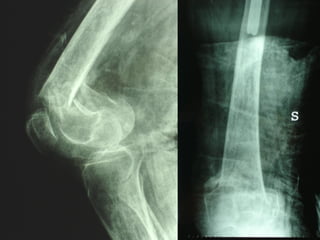

INDICAZIONI COMUNI Fratture sovracondiloidee Fratture intercondiliodee Fratture diafisarie distali PARTICOLARI Fratture con grave osteoporosi Fratture periprotesiche

VANTAGGI CHIRURGIA MININVASIVA Mini Open Inserimento della placca sottocutaneo per scivolamento Viti percutanee Preservazione dei tessuti molli Ridotto danno vascolare Rapida ripresa funzionale

F, 68 y

LISS  NCB

NCB